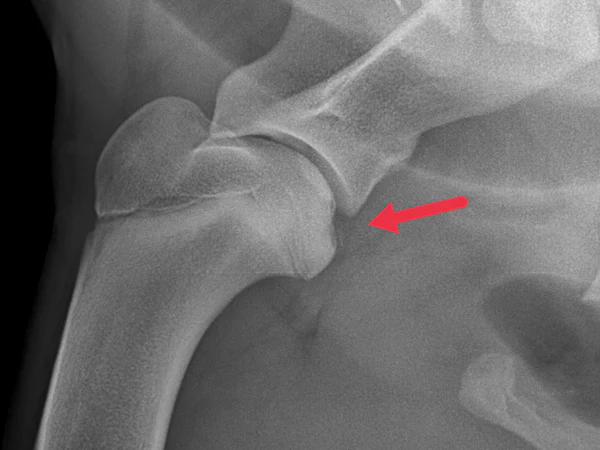

OCD tanısı röntgen, tomografi, MRG ve artroskopi ile koyulabilir. Fakat genellikle uzman bir göz tarafından yalnızca röntgen grafilerine bakılarak diğer tetkiklere ihtiyaç duymadan tanı koyulabilecektir. Yalnızca tek tarafta topallık olsa bile diğer omzun da grafilerinin alınması büyük önem taşır. Çünkü genetik faktörlere bağlı OCD her iki tarafta da olabilir. Genellikle gecikilmiş kronik olgularda eklem fareleri, ve ileri derecede osteoartrit görülür.